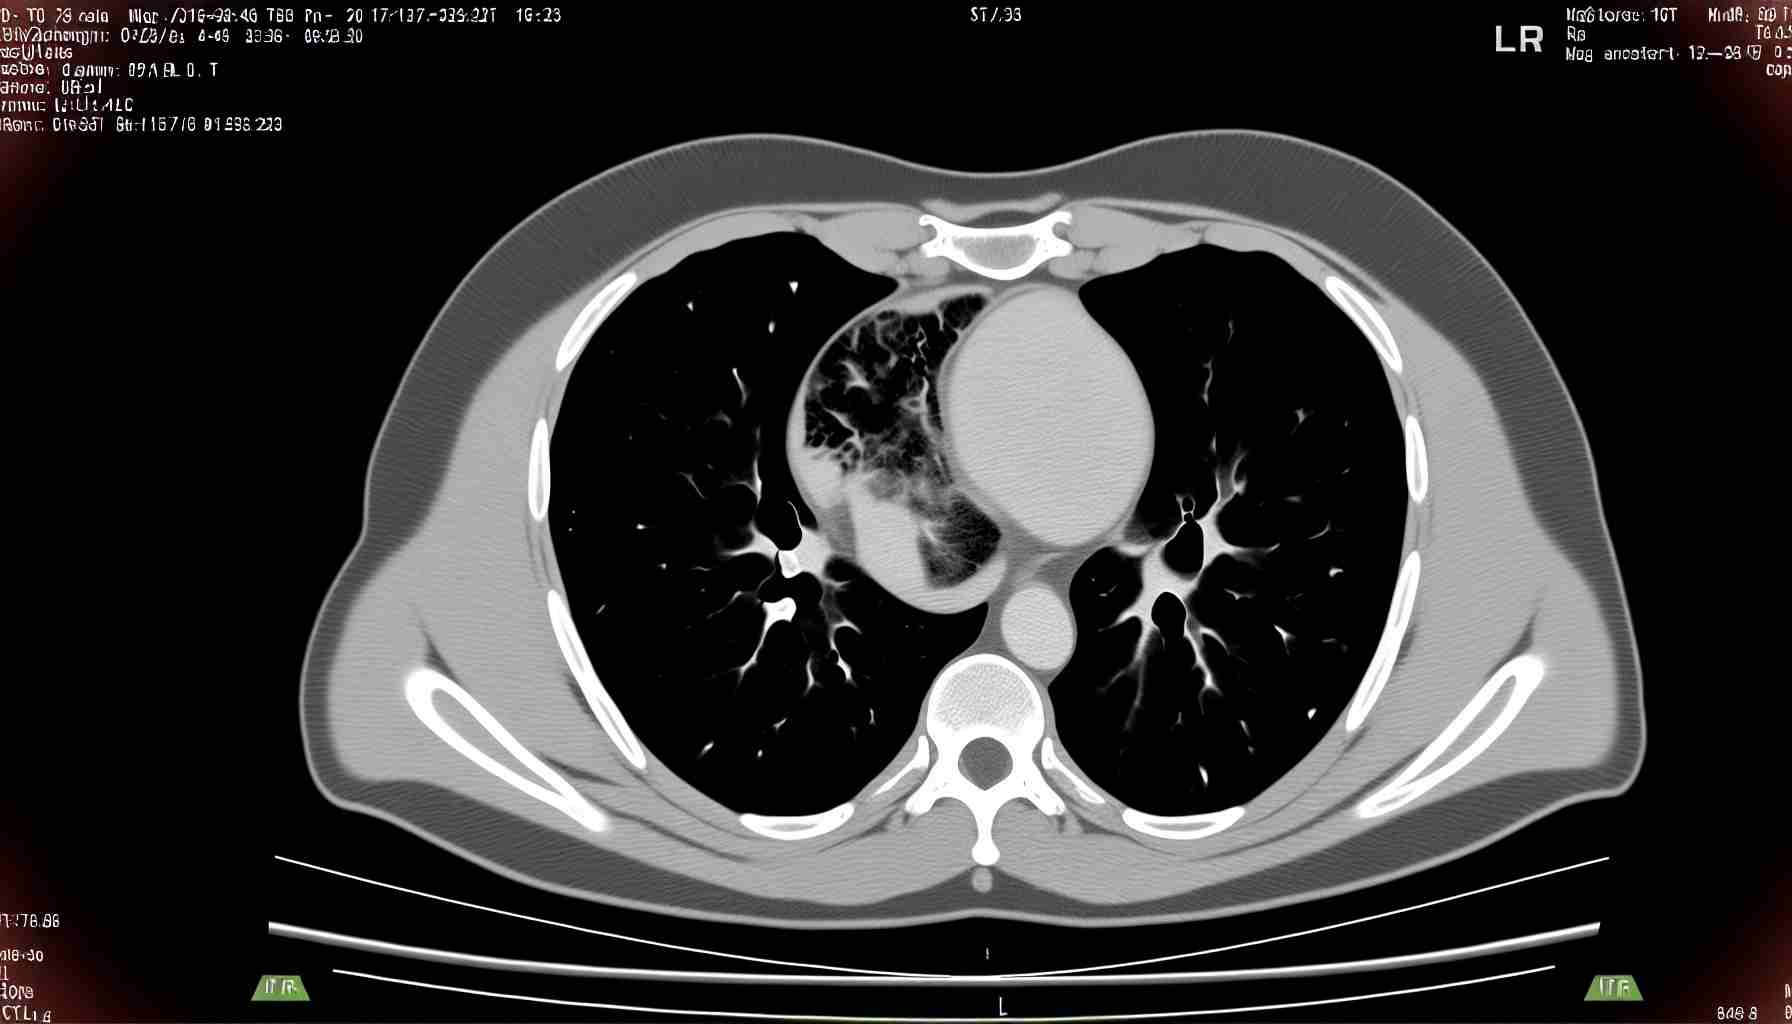

Нейробластома у детей – это опухоль, которая поражает симпатическую нервную систему и формируется из нейробластов – зародышевых нервных клеток. В 97% случаях патология развивается у пациентов, которые не достигли 15-летнего возраста.

Процесс выздоровления при нейробластоме зависит от ранней диагностики и лечения, которое часто затруднено из-за отсутствия клинических проявлений на ранних этапах. Обычно патологический процесс выявляется при достижении новообразованием больших размеров. Пациенту назначается индивидуальная схема лечения.